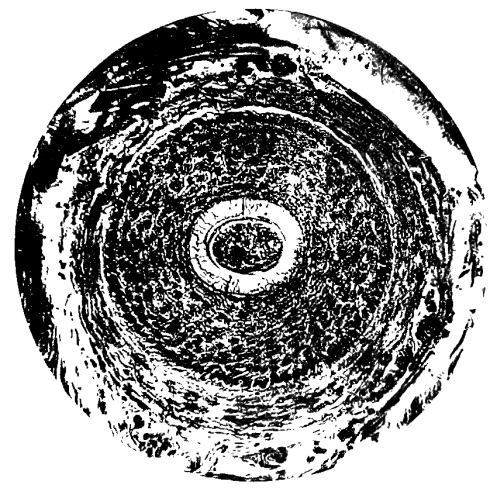

Plate showing Centre of Ossification in the Lower Epiphysi of PAGE

Femur in full time Fœtus To face 64